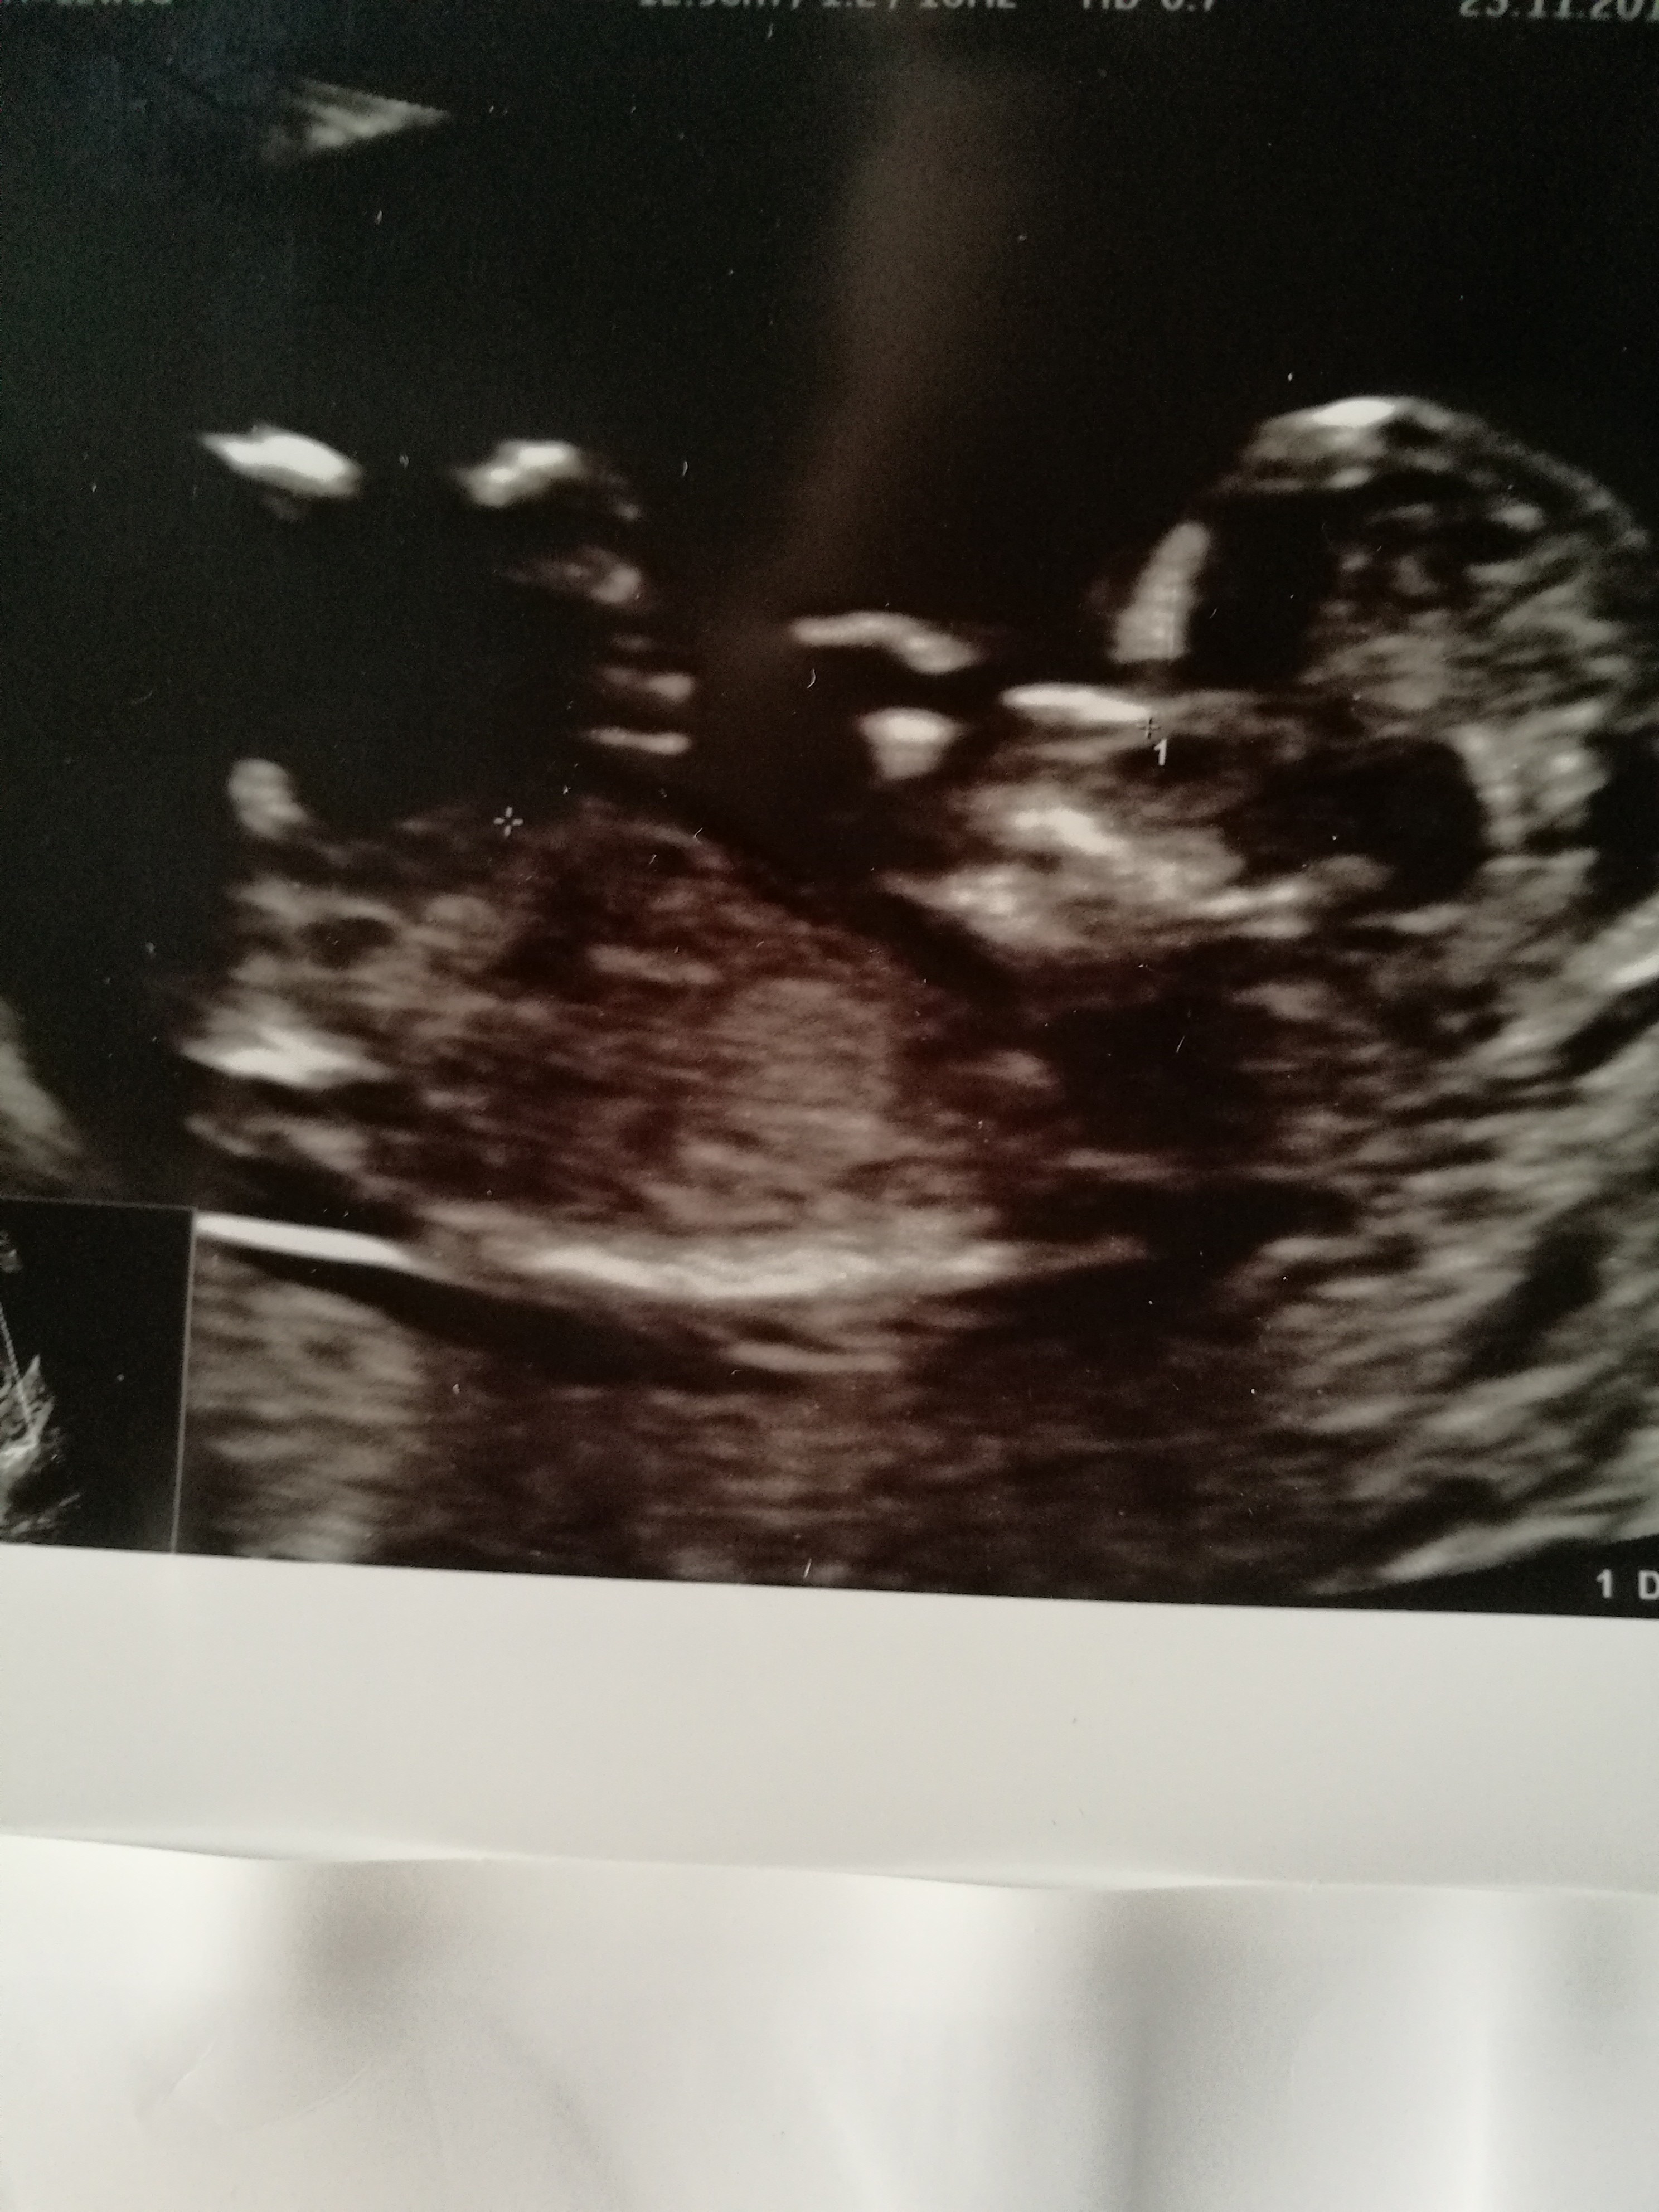

Mnie wczoraj lekarz powodzial że będzie chłopiec. Jestem w 14w3d szczerze mam jeszcze nadzieję że jednak się pomylił. A wy co myślicie??

Załączniki

• IMG_20181130_150924.jpg

IMG_20181130_150924.jpg

1,4 MB · Wyświetleń: 1 285